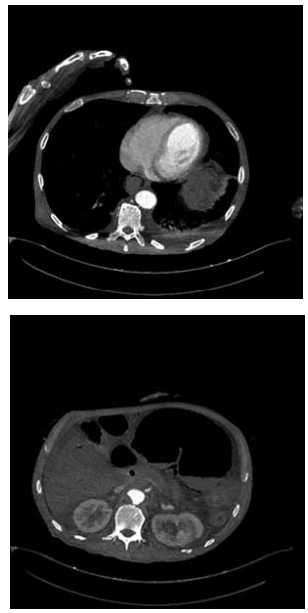

Paciente de 78 anos, hipertenso, tabagista, é admitido no pronto-socorro em choque séptico de instalação rápida, associado à dor abdominal súbita e distensão. Realizada tomografia computadorizada de abdome a seguir:

Qual o diagnóstico mais provável baseado na interpretação da imagem e no quadro clínico?